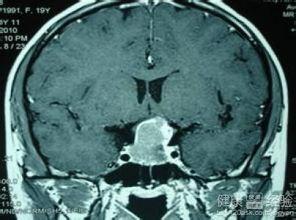

在手术前,患者需要接受一系列的检查,以确保手术的顺利进行。这些检查包括但不限于:血液检查、影像学检查(如MRI、CT等)、内分泌功能检查等。通过这些检查,医生可以了解肿瘤的大小、位置、性质以及患者的身体状况。